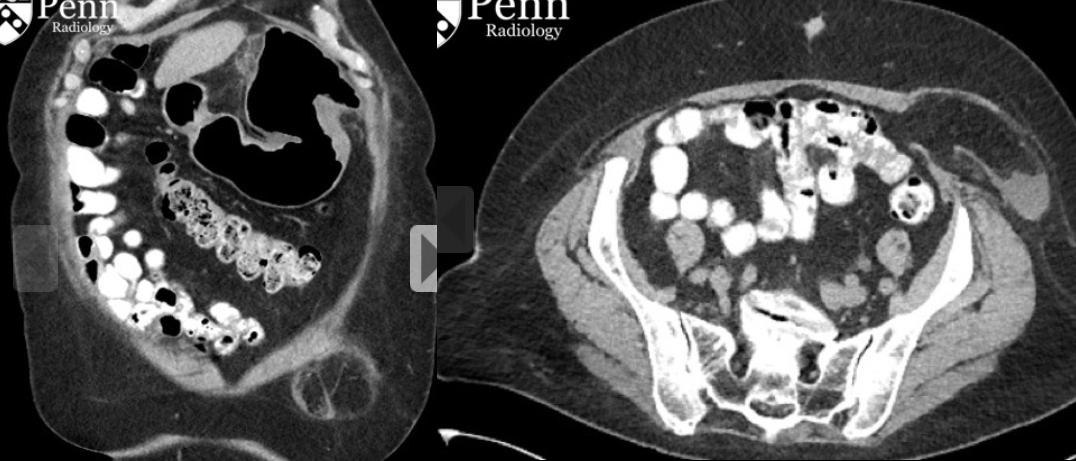

Masculino, 62 anos, 2 dias após colecistectomia.

Material hemostático na fossa da vesícula biliar pós colecistectomia.

Aspecto de bolhas de gás distribuidas de forma linear, uniformemente compactadas.

Sem realce da parede e sem nível liquido (diferente do abscesso)

Pode mascarar complicações da cirurgia (ex perfuração duodenal). Neste caso havia perfuração duodenal mascarada pelo material, que ao ser reabsorvido (5 dias após), deixou evidente o pneumoperitôneo e o extravasamento de contraste oral para a fossa da vesícula biliar.